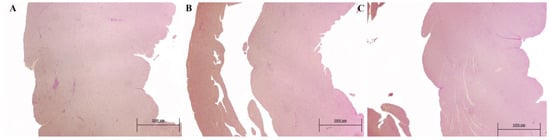

3.4. Histopathology Results